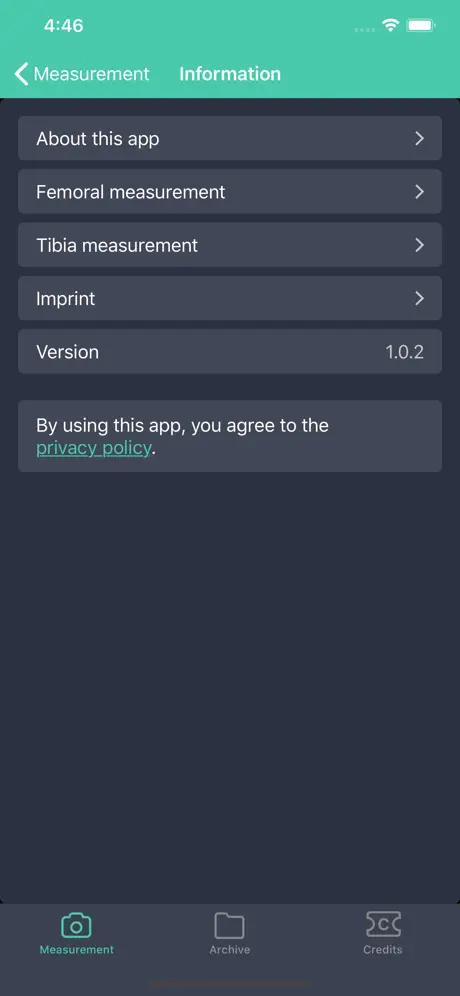

Информация о приложении

- Категория

- Medical

- 1.0.2 (5 лет назад )